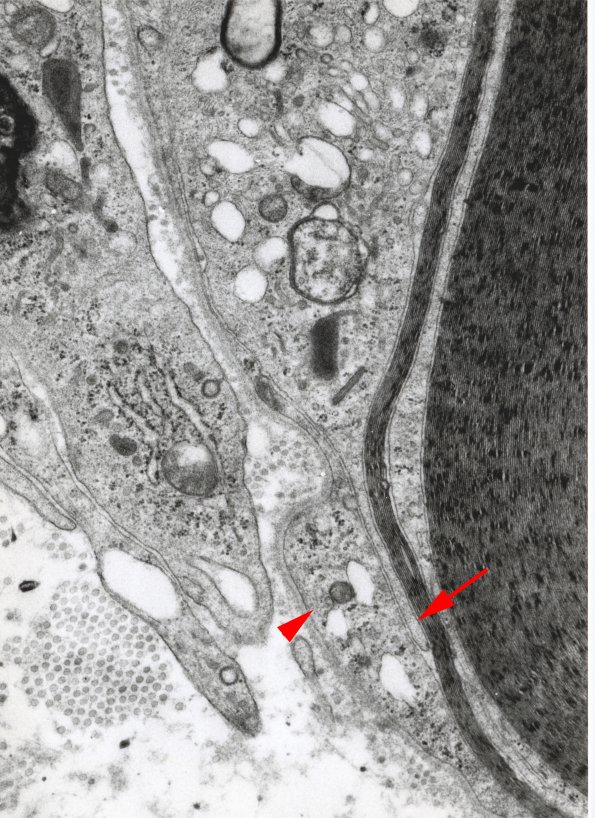

This is a higher magnification image from the arrowhead region of image #1D1. It shows a macrophage process (arrow) separating the myelin from the overlying Schwann cell cytoplasm (arrowhead). (electron micrograph)